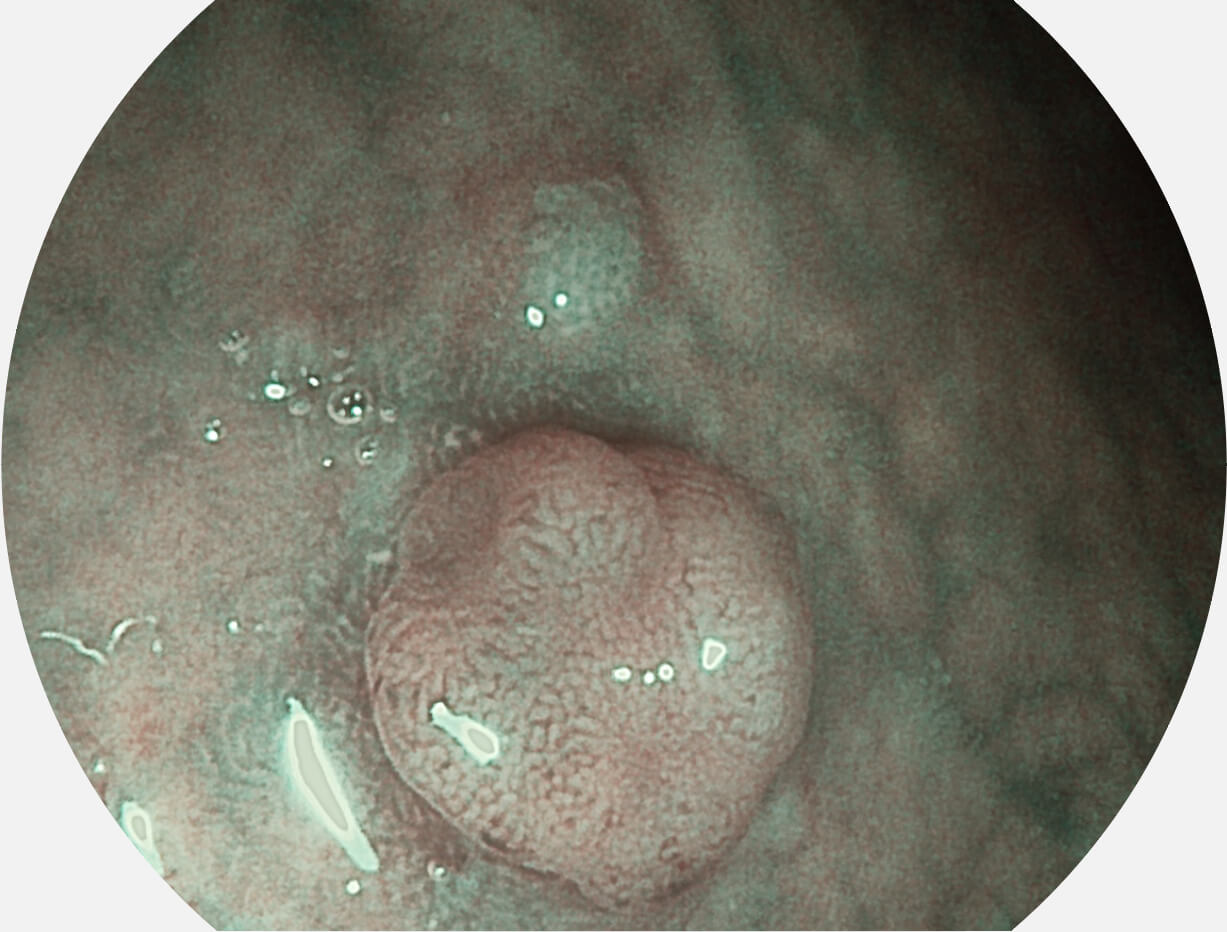

白光图像

VIST图像

强调浅层黏膜结构的同时,保证照明亮度和提升浅层微血管与中层血管颜色对比度,病变边界更清晰。

采用光路合束技术,光谱自由度高,实现了更丰富的照明模式,染色模式SFI及VIST,从远景到近景,助力消化道早期疾病诊断。